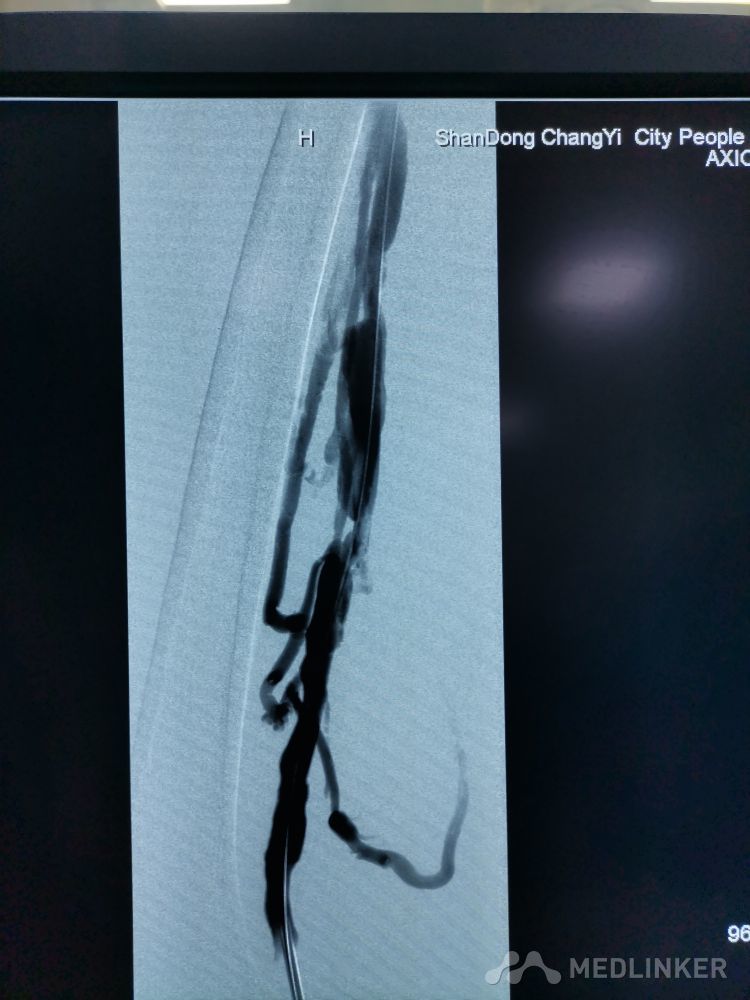

重视髂静脉压迫综合征。不同的临床表现,相同的病因,均为髂静脉压迫所致。第一例,表现为下肢静脉曲张伴溃疡,造影证实,髂静脉支架置入后解决。第二例,表现为左侧髂股静脉血栓,置管溶栓并髂静脉支架置入开通血管。第三例,下肢深静脉血栓后遗症,外院已行髂静脉支架置入,但皮肤营养情况仍持续加重,开通股浅 ,可见病变局部异常坚硬。精准施治,对症下药。